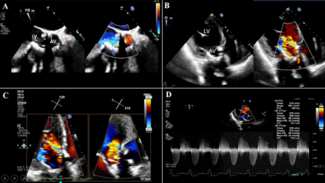

Clinical Images

03/06/2026

Leila Alizadeh, MD; Maria Eleni Drosou, MD; Takayuki Onishi, MD; Roya Anahita Mousavi, MD; Amit Hooda, MD; Sahil Khera, MD, MPH; Lucy M. Safi, DO; George D. Dangas, MD, PhD; Gilbert H.L. Tang, MD, MSc, MBA; Samin K. Sharma, MD; Annapoorna S. Kini, MD; Stamatios Lerakis, MD, PhD

An 80-year-old man presented with dyspnea. Nine years earlier, he had undergone transcatheter aortic valve replacement with a 29-mm Evolut R self-expanding valve (Medtronic) following aborted surgical aortic valve replacement due to extensive...